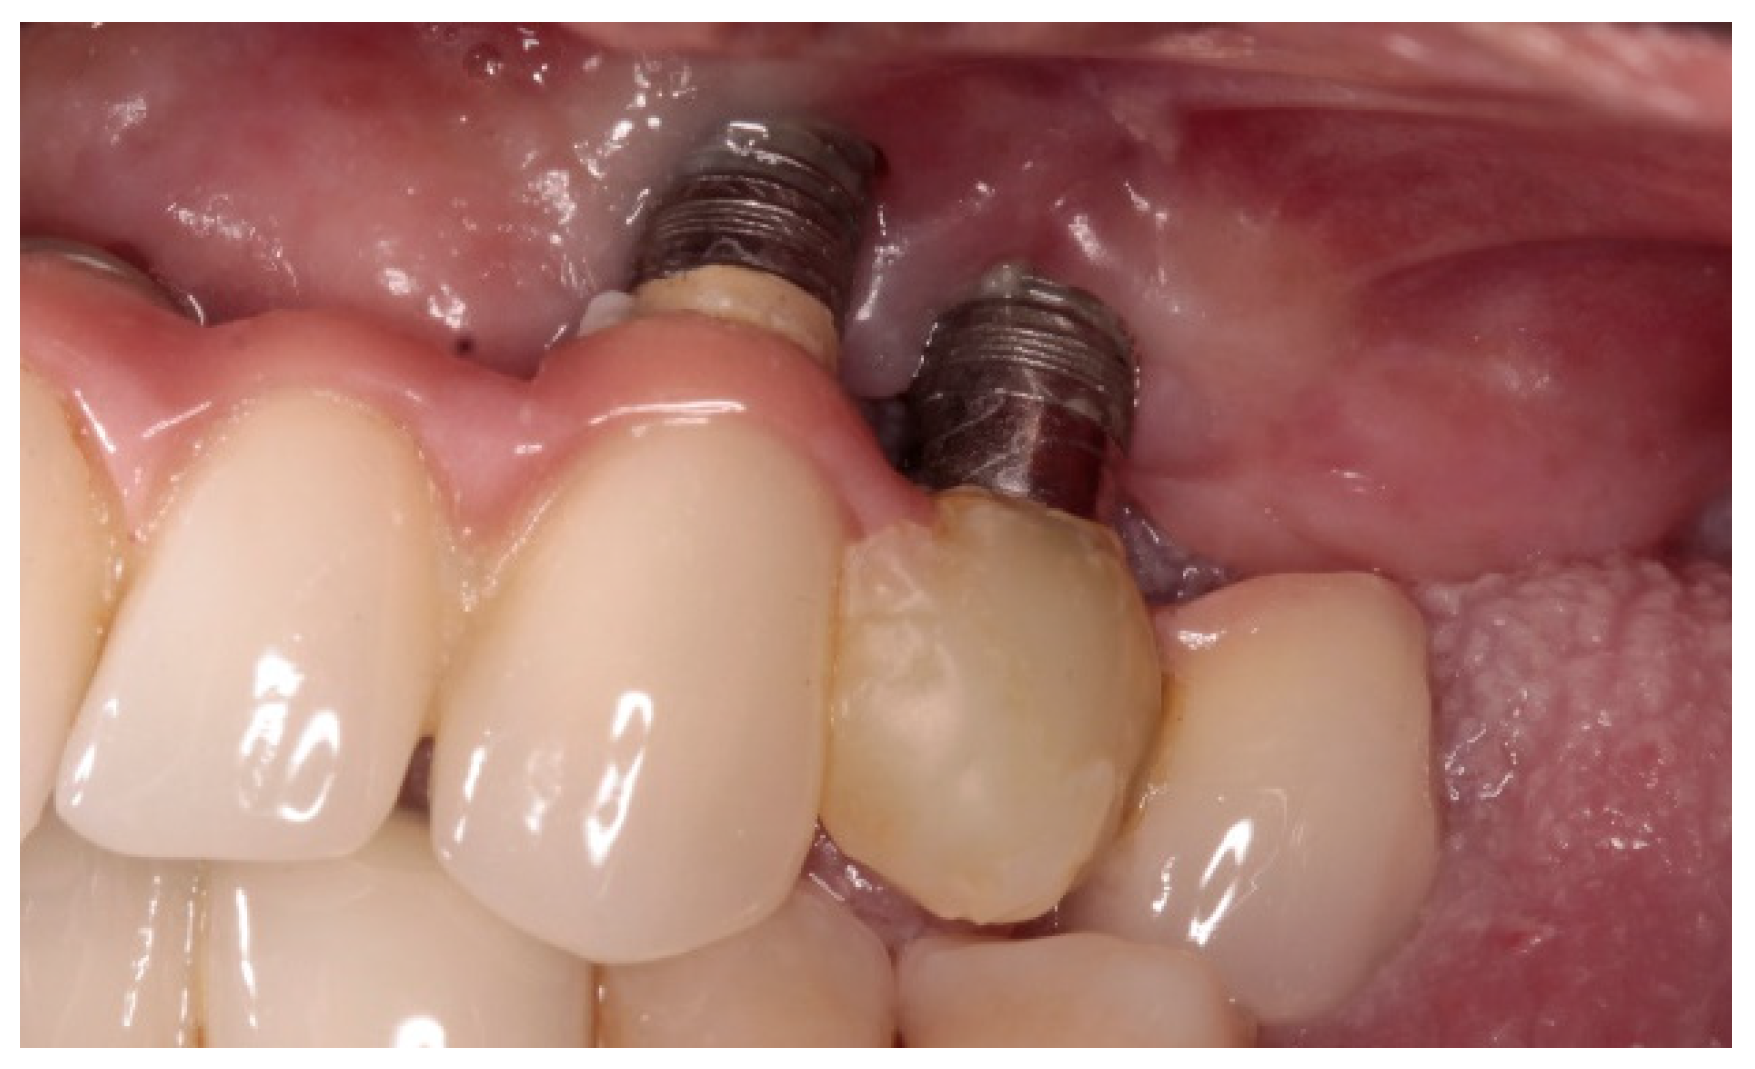

:1. Introduction

2. Method and Materials

2.2. Setting and Participants